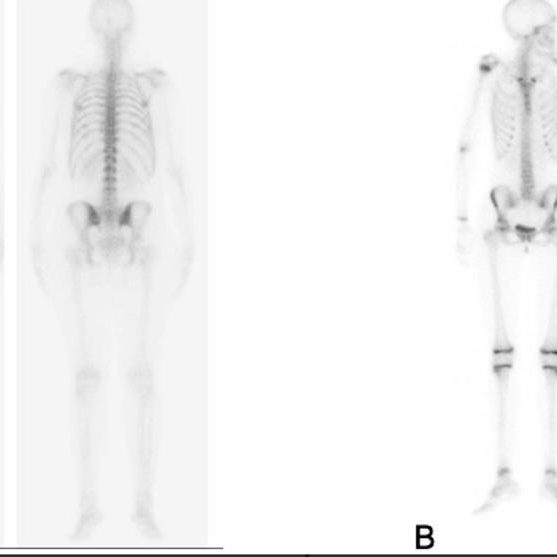

Una gammagrafía ósea es una prueba de diagnóstico por imágenes de medicina nuclear que ayuda a diagnosticar y controlar varios tipos de enfermedades óseas. El médico puede solicitarte una gammagrafía ósea si tienes dolor óseo inexplicable, una infección ósea o una lesión ósea que no puede verse en una radiografía estándar.

Una gammagrafía ósea también puede ser una herramienta importante para detectar el cáncer que se ha esparcido (metastatizado) al hueso desde la ubicación original del tumor, como la mama o la próstata.

Una gammagrafía ósea implica inyectar una cantidad muy pequeña de material radiactivo (marcador) dentro de una vena. La sustancia viaja a través de la sangre hasta los huesos y órganos. A medida que esta va desapareciendo, emite un poco de radiación. Esta es detectada por una cámara que lentamente escanea el cuerpo.

Toma imágenes del marcador que hay en sus huesos. El técnico puede solicitarle que cambie de posición durante el procedimiento. Esto ayuda a obtener imágenes desde diferentes ángulos. Una gammagrafía ósea de todo el cuerpo tarda aproximadamente 1 hora en completarse.